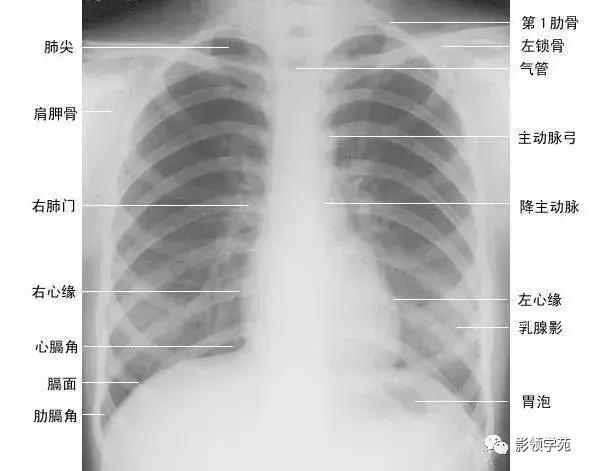

正常胸廓由软组织与骨骼组成,两侧对称(如下图)。

1、胸锁乳突肌及锁骨上皮肤皱褶 胸锁乳突肌起自胸骨柄及锁骨内端,向后上方斜行,止于乳突,在两肺尖内侧形成外缘锐利且较均匀的致密阴影。在胸骨头和锁骨头及锁骨之间形成一个小三角间隙,叫锁骨上窝或胸锁乳突肌间隙。当颈部偏斜时,两侧胸锁乳乳突肌阴影可不对称,勿误为肺尖部病变。锁骨上皮肤皱褶为与锁骨上缘平行的薄层软组织影,其厚度为3~5mm,内侧与胸锁乳突肌阴影相连,略成直角,系锁骨上皮肤及皮下组织的投影。

2、胸大肌起于锁骨的外侧分,胸骨和第1~6肋软骨,肌束行向外上方,至于肱骨大结节嵴。在肌肉发达的男性,于两肺中部的外侧形成扇形均匀致密影,下缘锐利呈斜行曲线,自肺野伸向腋部,与腋前皮肤皱褶相延续。

3、乳房及乳头 女性乳房于两下肺野形成半圆形的密度增高影,其下缘清楚,并向外与腋部皮肤连续,上缘不清,且密度自下而上逐渐变淡以至消失,其位置随年龄的增长而下垂,一般两侧对称。乳头在两下肺野相当于第5前肋间处形成边缘清楚的小圆形致密阴影,乳房越薄,乳头影境界越清晰,其特点亦为左右对称。青春期乳头呈半球状,约在第2~6肋之间。妊娠期乳腺可明显增大,至哺乳期结束后,乳房逐渐缩小,失去弹性而下垂,到老年期,乳房逐渐萎缩。

1、正位肺门影后前位胸片上,肺门位于两肺中野内带第2~4前肋间处,通常左侧肺门比右侧高1~2cm,两肺门的大小和密度大致相等。

(1)右肺门可分为上、下两部。上部约占113,由上肺静脉、上肺动脉及下肺动脉后回归支构成。上肺静脉下后干构成右上肺门的外缘;右肺门下部

约占213,由右下肺动脉干构成,其正常宽度不超过15mm,沿中间段支气管外缘平行向外下走行。右肺门上、下部相交形成一钝的夹角,称肺门角,正常该角顶清晰。

(2)左肺门亦分为上、下两部。上部由左肺动脉及其分支、左上叶支气管和左上肺静脉及其分支构成;下部由左下肺动脉及其分支构成,常被心影所遮盖(如下图)。

2、侧位肺门 侧位胸片上,两饲肺门阴影大部分重叠,若以侧位气管轴线为界,右肺门略信其前下,左肺门大部分在其后上。侧位肺门影前缘为右上肺静脉干形成的椭圆形阴影,前后径为2cm左右;中间纵行透亮区为气管及气管分叉,其内圆形透亮影表示支气管开口,右侧在上,左侧居下;后上缘为左肺动脉弓,下缘由两下肺动脉构成下行的树枝状影。因此,侧位肺门影似一尾巴拖长的“逗号”(如上右图):

(七)肺纹理

肺纹理为自肺门向肺野呈放射状分布的树枝状阴影,它主要是肺动脉的投影,肺静脉、支气管和淋巴管也参与形成。平片可显示肺纹理的多少,粗细.分布,有无扭曲、变形与移位等。肺纹理由肺门向外围延伸,逐渐变细,至肺野外带渐细小而稀少,距侧胸壁内缘约1cm范围内的肺野基本无肺纹理可见(图下图)。